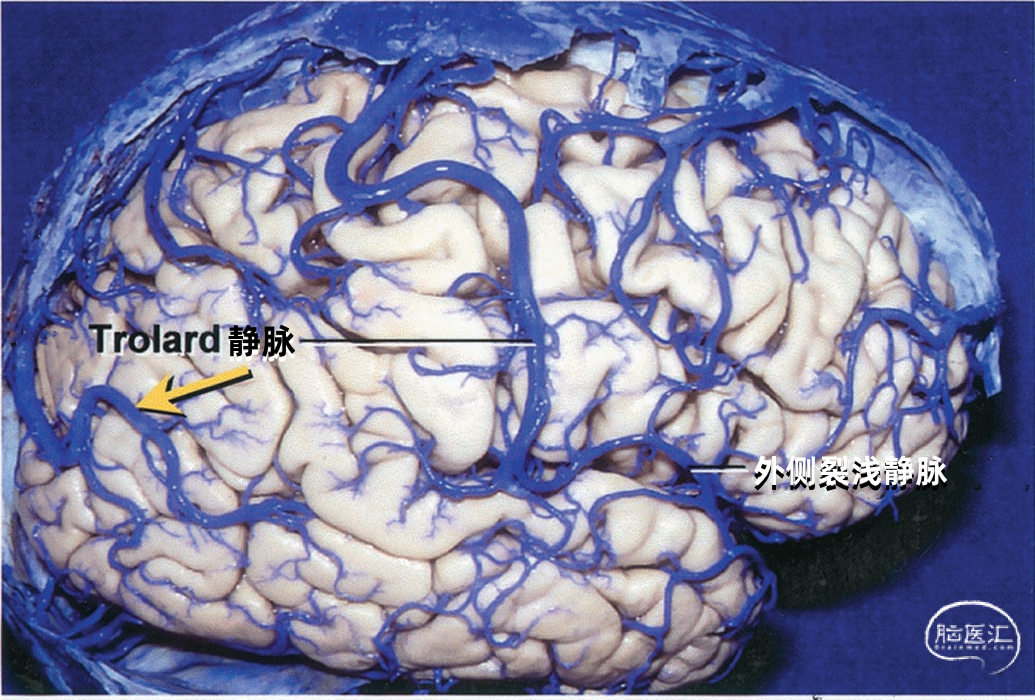

大脑外侧面最大的静脉是Trolard、Labbé、外侧裂浅静脉。 Trolard静脉是最粗大的吻合静脉,连接外侧裂静脉和上矢状窦。Labbé静脉则是连接外侧裂浅静脉和横窦的最粗大吻合静脉。外侧裂浅静脉沿外侧裂表面走行,而且主要沿蝶骨嵴汇入硬膜窦(蝶顶窦或海绵窦)。 虽然Trolard、Labbé静脉和外侧裂浅静脉大小可能相同,但更常见的是其中一支或两支血管比较粗大,而剩下的则细小甚至缺如。通常左右两侧血管的大小并不对称。

▼1.Trolard静脉

Trolard静脉又称上吻合静脉,是跨越额叶和顶叶,连接外侧裂与上矢状窦的最大吻合静脉。 在我们研究的20例半球标本中,发现15例Trolard静脉的位置相当于中央前静脉、中央沟静脉和中央后静脉,最常见的位置是中央后静脉水平。最靠前的Trolard静脉位于额前静脉水平,连接上矢状窦的前部和外侧裂浅静脉的前部。最靠后的Trolard静脉位于顶前静脉水平。 Trolard静脉通常以单干向前走行,汇入上矢状窦,与血流相反方向。通常Troland静脉在将要汇入上矢状窦前接受其他一些静脉的回流,它的下端通常以单一通道与外侧裂静脉相沟通,但也可在额叶和顶叶凸面的下部分成许多分支加入外侧裂浅静脉。有时会有两条同样大小的Trolard静脉连接外侧裂血管和上矢状窦之间。

下图示(右侧)大脑半球的引流静脉汇入上矢状窦和横窦。外侧裂浅静脉细小。一支细小的Trolard静脉连接上矢状窦和外侧裂。

下图示(右侧半球)单支粗大的Trolard静脉走行于中央沟区,连接上矢状窦和外侧裂浅静脉。此标本上Labbé静脉发育不完全,但是有一支来自顶后部和颞后部的粗大静脉(黄色箭头所示)进入上矢状窦。